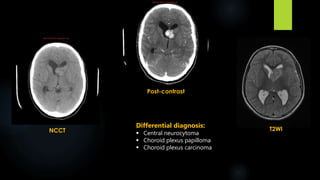

NCCT

Post-contrast

T2WI

Differential diagnosis:

 Central neurocytoma

 Choroid plexus papilloma

 Choroid plexus carcinoma